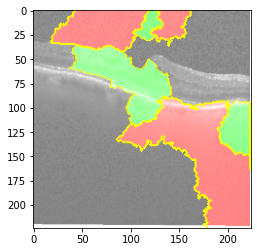

Fig 6, 7, 8 and 9 depicts the visualization of correct predictions by our proposed CNN model where fig 6 is class CNV, fig 8 is class DME, fig 7 is DRUSEN and finally, fig 9 is NORMAL. Here the first photo in every class is the original image. The LIME map of our suggested model’s prediction is shown in image B whereas in image C the positive region is highlighted in specific sections on the original image. For Image D we have increased the number of features from 5 to 10 thus more regions have been predicted as the positive region which is highlighted in green. After increasing the features from 5 to 10, some of the regions are predicted wrongly. The red regions represent the output of incorrect prediction. The following image represents the Grad-CAM heatmap highlighting the regions with our model’s prediction.